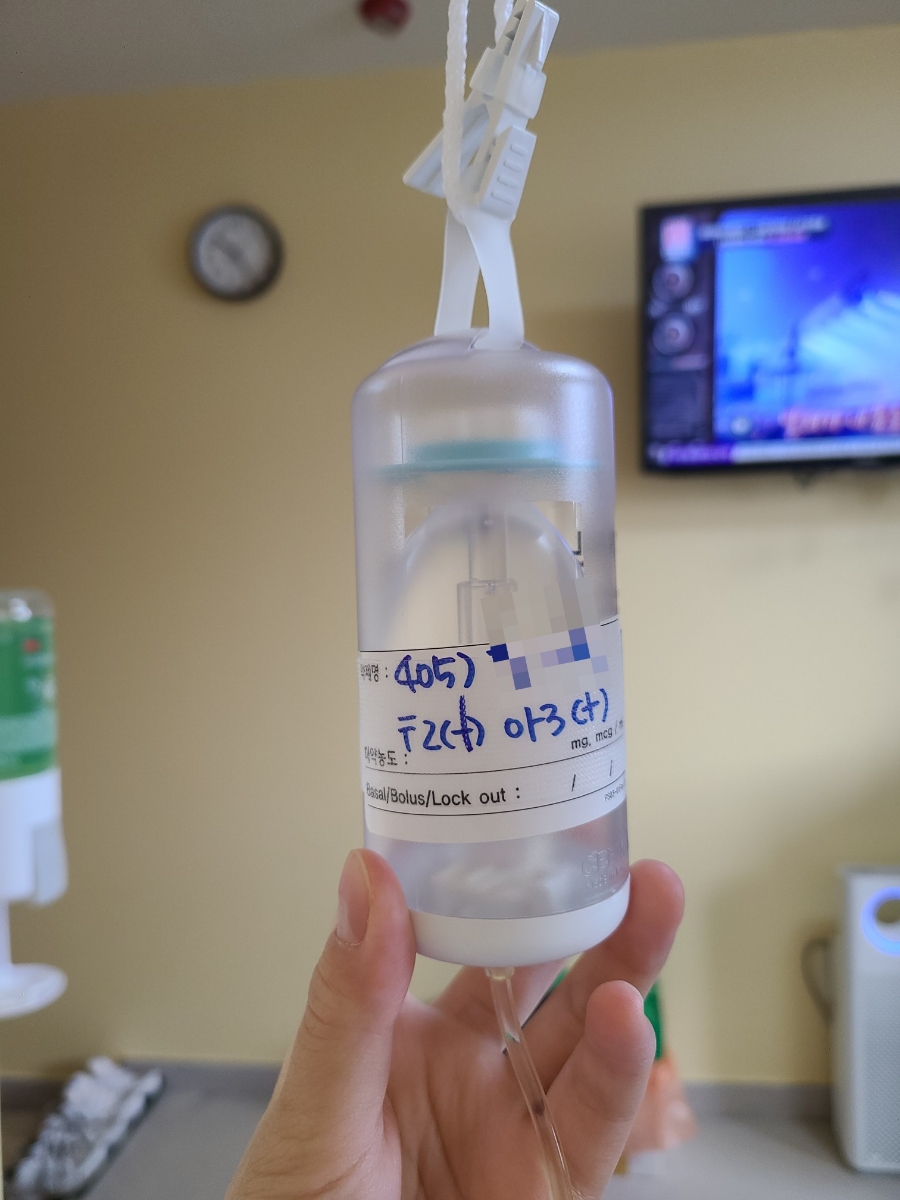

가습기를 틀고 잤는데 일어났더니 목이 건조해.’내일 아침은 실패했구나’라는 생각이 들었다.당연히 병원 내에서 숙면을 취하는 것은 불가능하지만(시간에 맞춰 혈압과 체온 등을 측정하기 때문에) 나름대로 나쁘지 않았다. 1인실 만세!! 어제 움직일 때마다 조금 아팠던 링거의 위치를 변경했다.

바꾸길 잘했다 바꿔서 그들은 어떻게 움직여도 하나도 아프지 않아!! 멍을 들었다. 나의 수술 예정 시간은 오전 9시.8시 30분까지 학부모 한 명이 상주해야 해서 어제 생일의 주인공인 엄마를 불렀다.8시 50분쯤 간호사가 5층 수술실로 가자고 했다. 걸어서 엘베타고행 회복실 앞에서 기관지를 확장시키는 흡입기 같은 것을 1분 동안 하라고 해서 했다.다 하고 5분정도 기다리면 수술실에서 저를 부르셔서 어머니와 헤어져 그대로 입실.수술실은 생각보다 작았다.수술상도 다 차려져 있더라.누워서 준비하고 있으면 마취과 원장이 와서 졸릴 것 같아요~라며 마취가스를 뿌렸지만 두 번 정도 마시고 나서 정신을 차려보니 회복실이었다.옆에 어머니가 앉아 있었다.조금 몽롱했지만 어머니에게 했던 이야기가 모두 생각난다. 와, 바로 기절했어 수술실이 생각보다 작다… 이런 얘기. 걸을 수 있을 것 같아서 일어났는데 제지 당해서 침대째 병실로 왔다.병실에 온 시간은 9시 40분?50분 정도였다.1시간도 안 걸렸네.병실에 오자마자 간호사 선생님이 혈압, 체온 등을 재서 거울에 편도선이 사라진 것을 확인하고 엄마가 입속 사진을 찍어달라고 했어ㅋㅋㅋㅋㅋㅋㅋㅋ